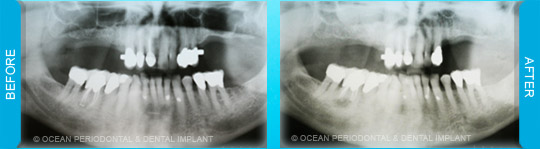

Implants to be placed in the posterior maxilla create a unique challenge when there is minimal bone height available inferior to the sinus floor. Such deficiencies occur due to sinus pneumatization and extraction atrophy of the bone. Fortunately, the lost height can be regained by elevating straightforward procedures to augment height.

On rare occasions, there is inadequate bone height to place the upper implants due to the sinus. Grafting procedures can increase the height to place the implants successfully without affecting the sinus.